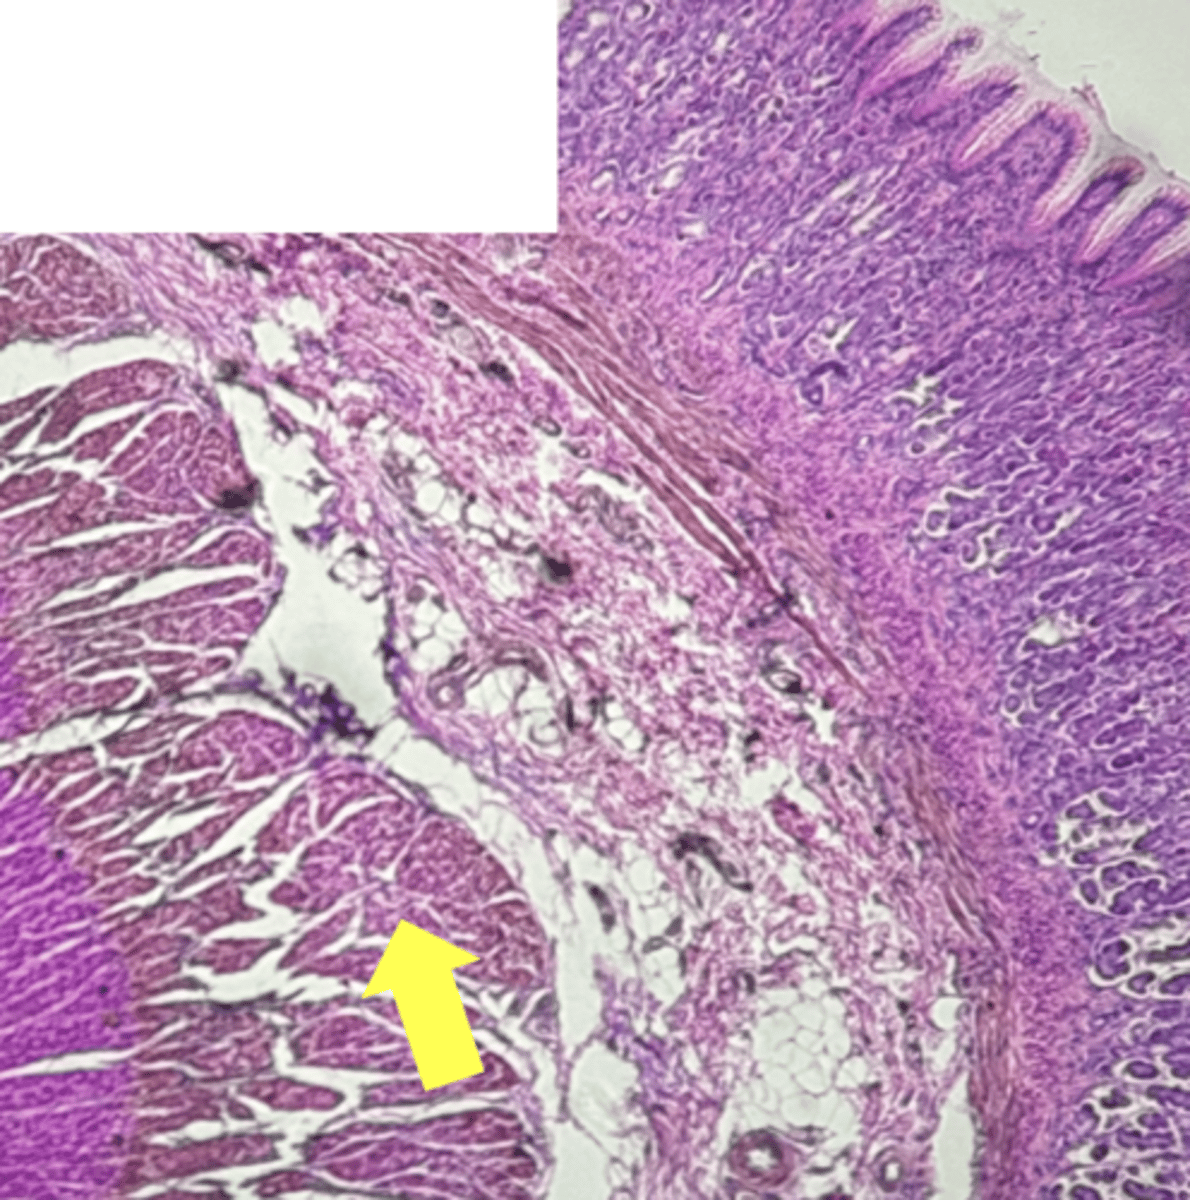

A- Esophagus

B- Stomach

Name the Tissue A & B

stomach

name the tissue

mucosa

(stomach)

submucosa

muscularis externa (3 LAYERS-KEY CHARACTERISTIC)

oblique layer

circular layer

longitudinal layer

simple columnar epithelium

gastric pits (KEY CHARACTERISTIC)

gastric glands (KEY CHARACTERISTIC)

Parietal cells- HCl (hydrochloric acid)

name the cell & what it secretes

Chief Cells- pepsinogen/pepsin

Lamina propria

muscularis mucosae

Esophagus

(esophagus)

muscularis externa

stratified squamous epithilium (KEY CHARACTERISTIC)